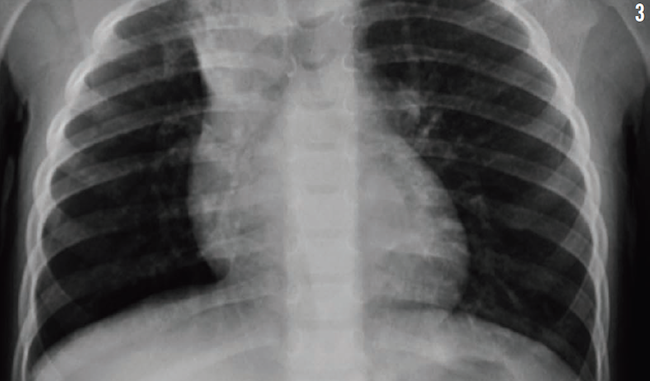

Treatment was started with parenteral clindamycin for presumptive aspiration pneumonia of the right upper lobe. All of her previous radiographs were reviewed (Figures 1-3), and a computed tomography scan of the chest was performed (Figure 4), the latter of which revealed bronchiectasis. Results of a quantitative sweat test were negative for cystic fibrosis, and results of immune function testing were normal.

Figure 3: Chest radiograph of the patient at 33 months of age.